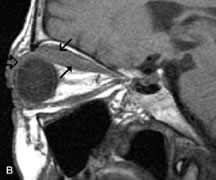

MRI is particularly helpful in the detection and characterization of subperiosteal hematomas of the orbit (Fig. 19). They are most commonly seen in the subperiosteal space of the superior orbit as well-defined masses following a traumatic injury. The signal intensity varies depending on the acute, subacute, or chronic nature of the hematoma, based on the stage of blood degradation. Fresh hemorrhages are hypointense on T1-weighted images and hyperintense on T2 images. Hematomas that are 1 to 7 days old are hypointense on both T1- and T2-weighted images. T1-weighted images of hematomas more than a week old are hyperintense due to the oxidation of deoxyhemoglobin to methemoglobin, whereas the T2 images remain hypointense.63

Fig. 19. A. T1- and (B) T2-weighted MR scans demonstrate a large acute subperiosteal hematoma (H) that lies between the cortical bone of the orbital roof and the inferiorly displaced periorthira (double arrow). The extracopal fat (arrow) and levator muscle are displaced inferiorly.